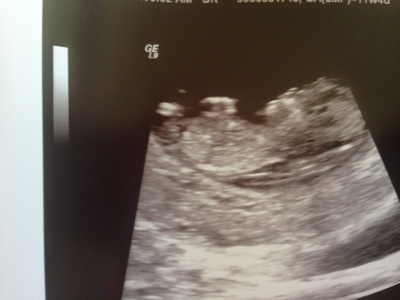

Hello! I'm new to this forum but I'd love to hear what you guess from our 12 week 0 day ultrasound. I really appreciate you taking the time to guess. Skull and Nub guesses would be great! Thanks so much!

Attachment 18912